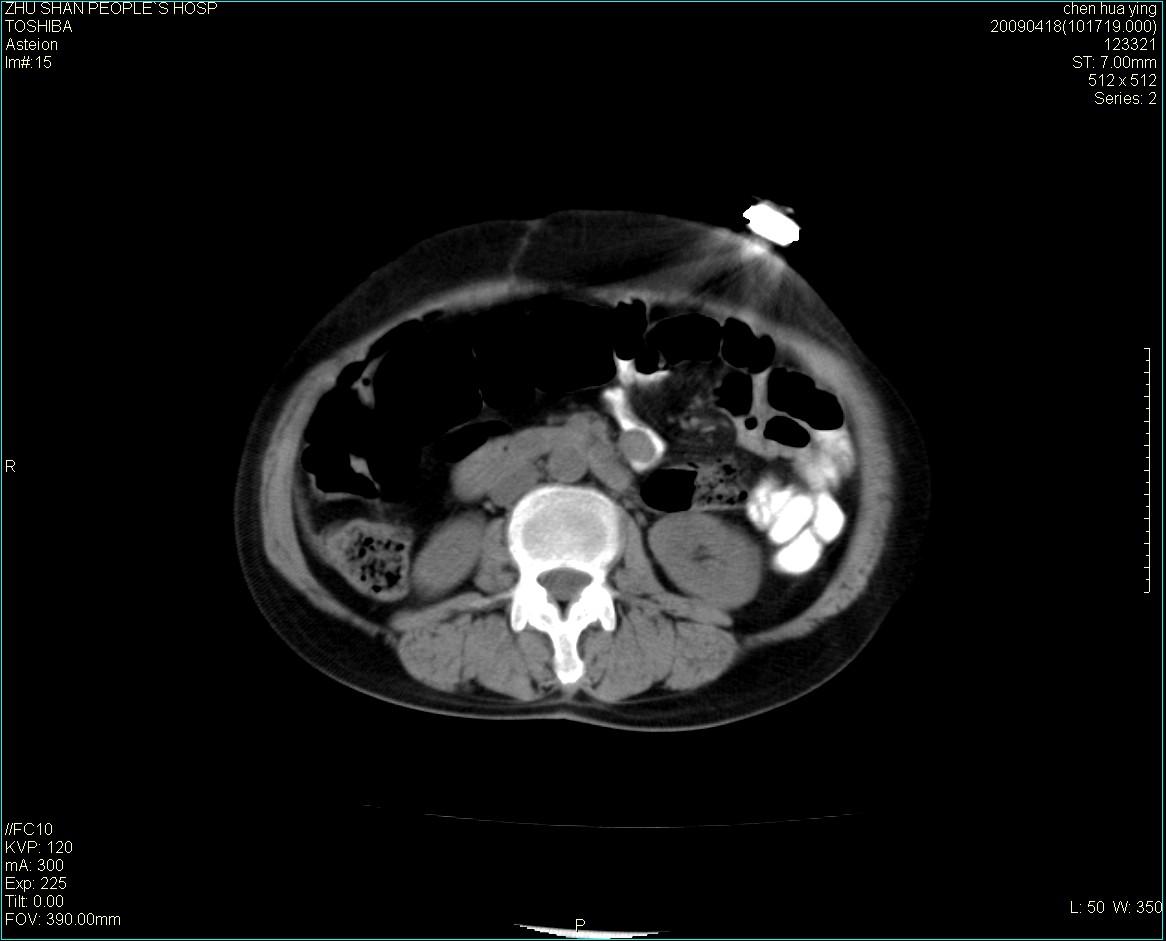

女性病人 65岁 腹部包块半年余结肠造影未见异常.

病灶略呈圆形有分叶状,上部层面呈实性,右侧见圆形低密度区,灶内见团块状钙化,病灶下方与肠管分境不清,考虑间质瘤可能性大,建议肠道准备后增强